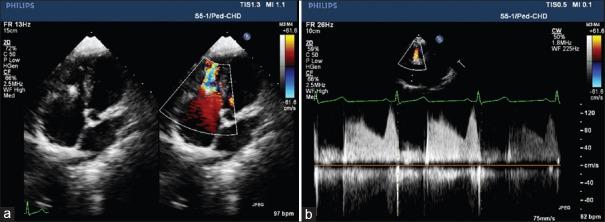

Asymmetrical septal occluder device (ASOD) has made percutaneous closure of ventricular septal defect an easy and effective management option. Although there are reports of aortic and tricuspid valvular regurgitation after deployment of ASOD, only few cases of tricuspid stenosis (TS) has been reported so far in the literature. We report a case of malaligned ASOD that occurred after successful device closure resulting in TS along with mild tricuspid and aortic regurgitation requiring surgical retrieval. Transesophageal echocardiography played crucial role in detecting the cause of tricuspid valve dysfunction besides providing continuous monitoring during the procedure. We intend to emphasize the need of echocardiographic evaluation of the tricuspid valvular apparatus and aortic valve during and after the device deployment even after the successful device closure to prevent this rare complication.

摘要

不对称性室间隔封堵器(ASOD)使经皮闭合室间隔缺损成为一种简便有效的治疗选择。尽管有报道称ASOD植入后出现主动脉瓣和三尖瓣反流,但迄今为止,文献中仅报道了少数三尖瓣狭窄(TS)病例。我们报告一例在成功进行封堵器闭合术后发生的ASOD位置不当病例,导致TS以及轻度三尖瓣和主动脉瓣反流,需要通过手术取出封堵器。经食管超声心动图除了在手术过程中提供持续监测外,在检测三尖瓣功能障碍的原因方面发挥了关键作用。我们旨在强调,即使封堵器成功闭合,在封堵器植入期间及之后,也需要对三尖瓣装置和主动脉瓣进行超声心动图评估,以预防这种罕见的并发症。